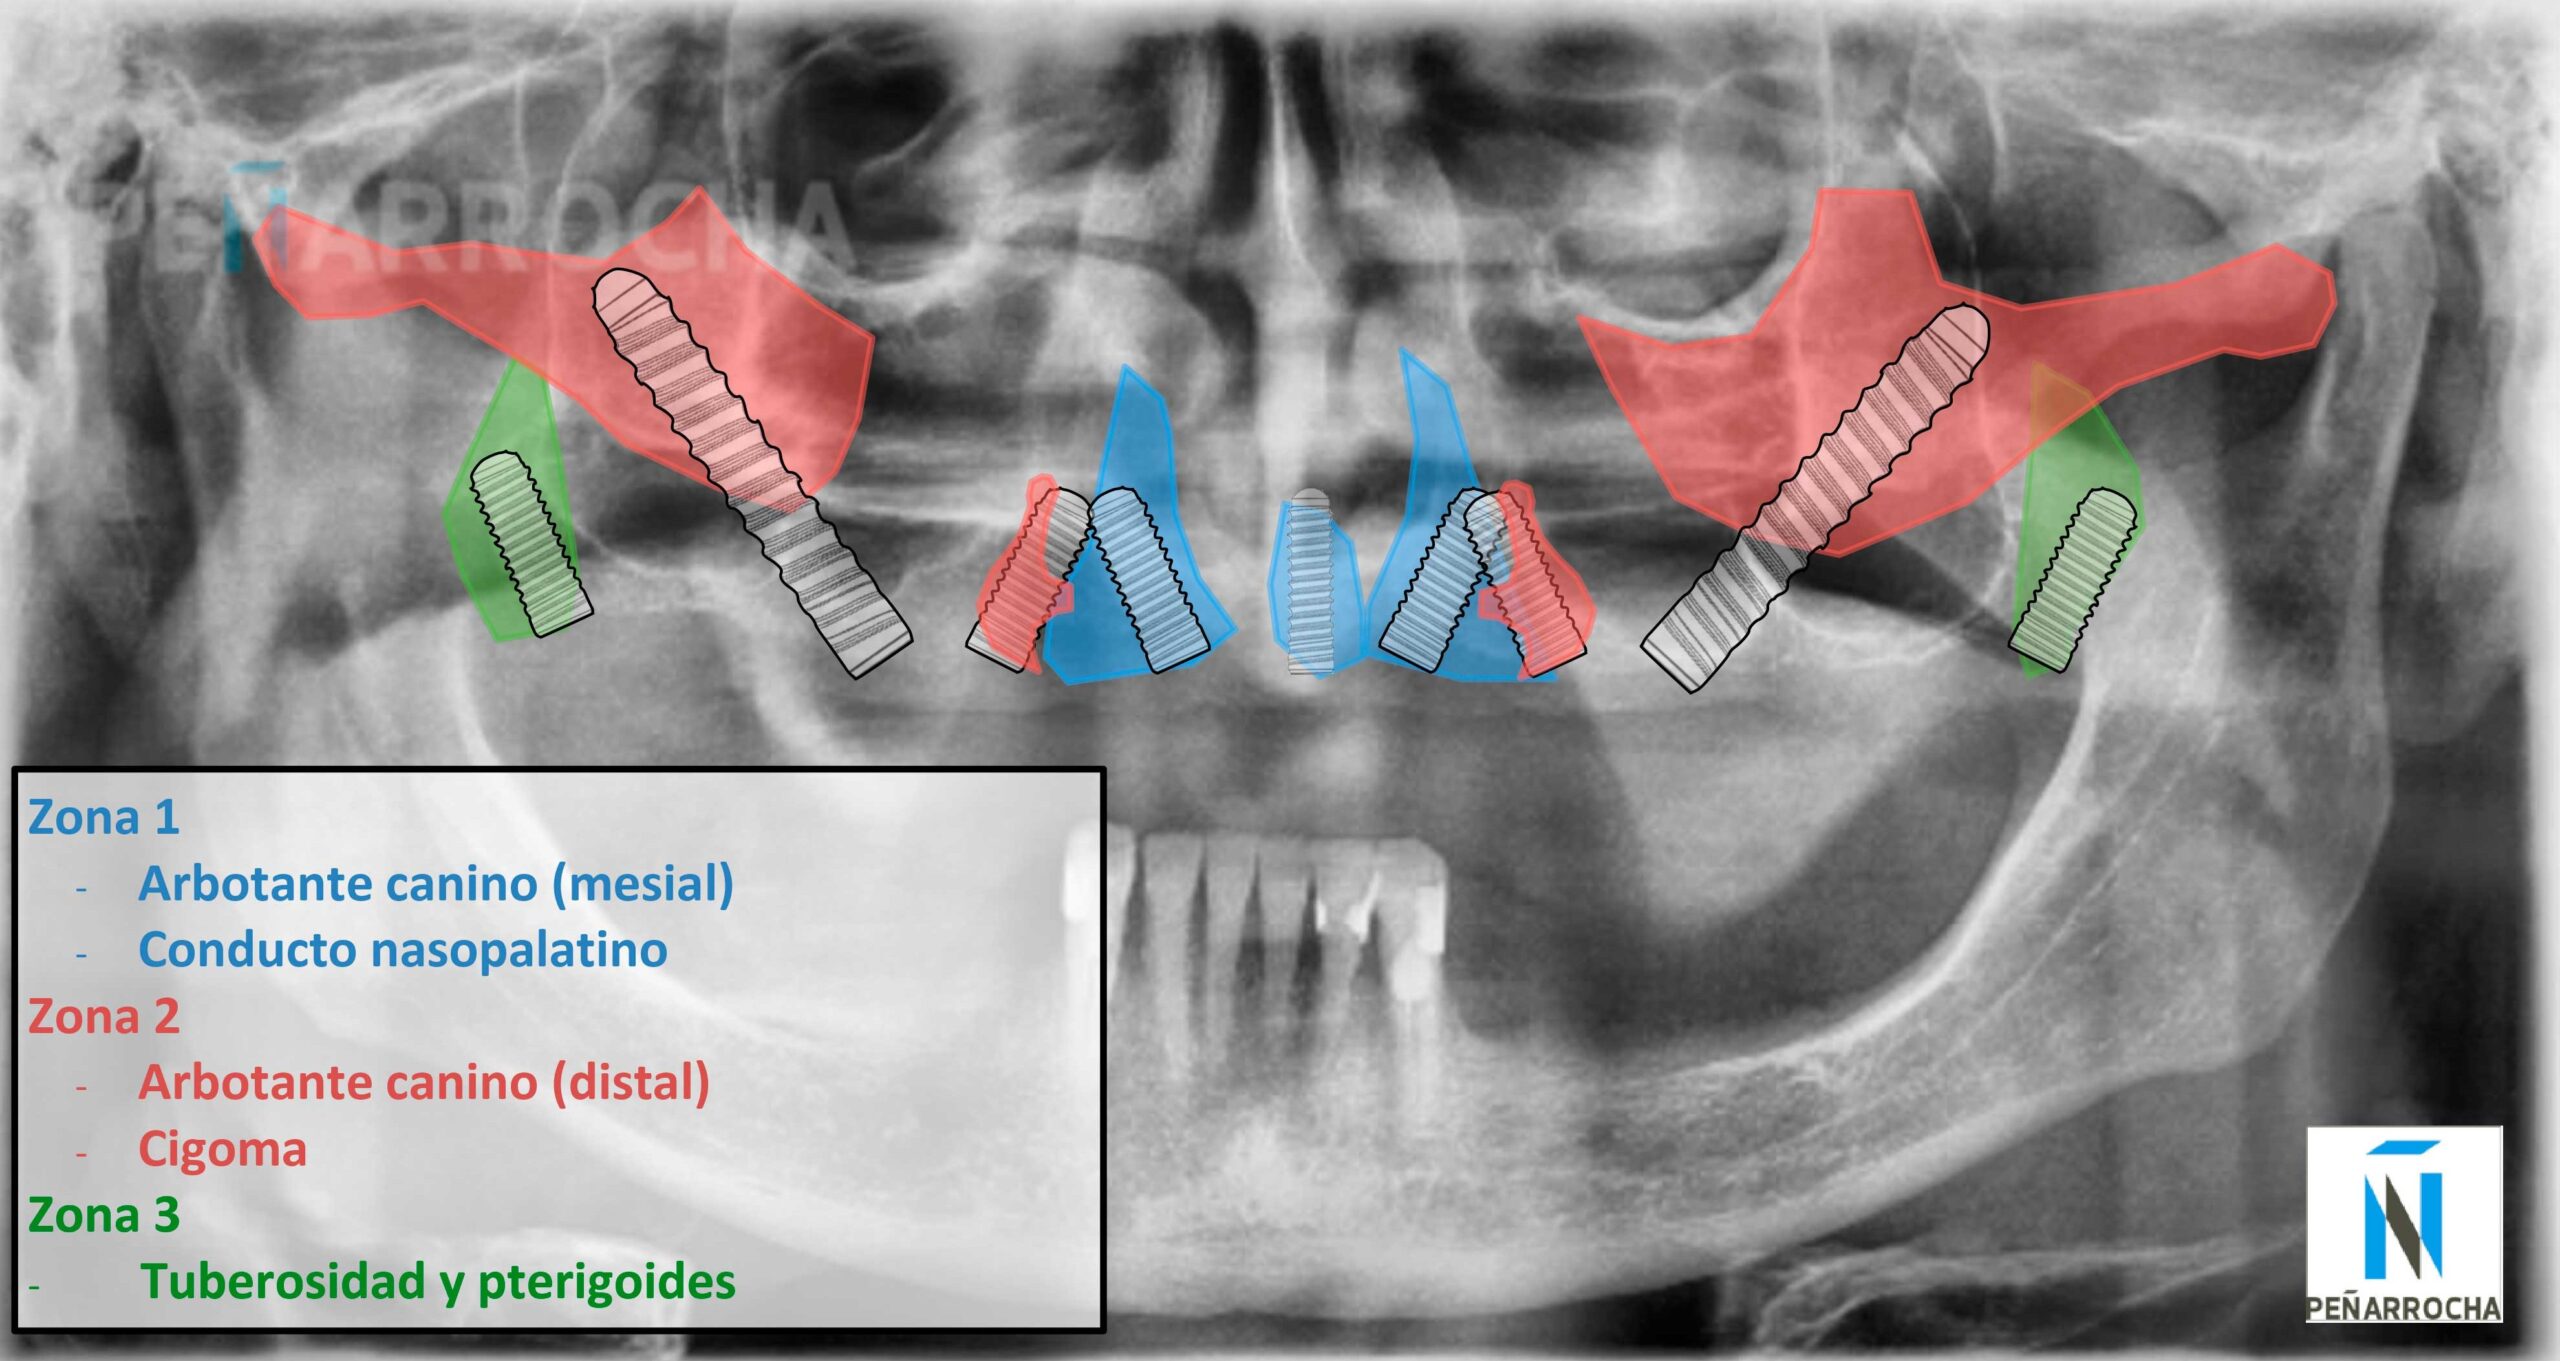

Hoy en día, existen técnicas avanzadas que permiten aprovechar el hueso remanente sin necesidad de recurrir a procedimientos más complejos como los injertos óseos. Una de las claves es la colocación de implantes en zonas estratégicas del maxilar, conocidas como arbotantes. En estas áreas, el hueso es más denso y resistente, actuando como una estructura natural capaz de soportar las fuerzas de la masticación.

Gracias a que suelen ser las últimas zonas en perder volumen óseo, permiten colocar implantes firmes y duraderos. De este modo, es posible rehabilitar la sonrisa y recuperar la función masticatoria incluso en situaciones de pérdida ósea avanzada.

Dónde se puede poner un implante dental con poco hueso

Implante dental con poco hueso maxilar superior

Los implantes cigomáticos, pterigoideos o palatinos permiten aprovechar zonas estratégicas con mayor calidad ósea, como los arbotantes maxilares.

Implantes nasopalatinos

Los implantes nasopalatinos se colocan en el canal nasopalatino para conseguir el mayor aprovechamiento de hueso. Se trata de una zona anatómica con buena densidad ósea en el maxilar superior para proporcionar un soporte adicional en rehabilitaciones complejas.

Implantes pterigoideos

Los implantes pterigoideos están indicados en casos de pérdida ósea severa en la zona posterior del maxilar superior. Se anclan en el hueso pterigoideo, evitando la necesidad de realizar injertos óseos o elevaciones de seno maxilar, acortando el tiempo de tratamiento.

Implantes cigomáticos

Los implantes cigomáticos están indicados en los casos de atrofia ósea más extrema. Se anclan en el hueso cigomático (pómulo), que ofrece una gran densidad y estabilidad, y se suelen combinar con implantes convencionales, evitando los injertos óseos.